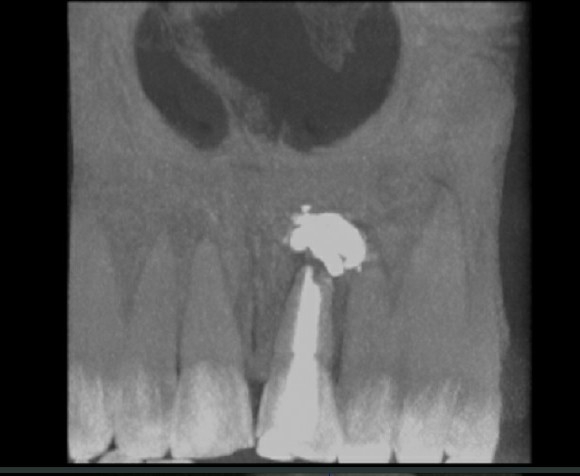

Спустя 30 месяцев пишу вам из отделения челюстно-лицевой хирургии, в общем пошел по вашему совету(вас не виню, совет то был дельный) к врачу и она мне там говорила что канал плохо был заплобирован и вскрыла канал отбелила(пришлось два раза отбеливать она ещё удивилась) и нафигачила в канал материала чтоб "хорошо" было заплобирован, всё это дело успешно через открытый корень уползло в десну и в итоге спустя 30 месяцев мне вырезали кисту. Снимок прилагается.

P.S. Зуб кстати спустя время потемнел опять, мне потом другой врач объяснил что было всё напрасно потому что зуб был долго заплобирован материалом темным и напитывался его цветом в итоге внутриканальное отбеливание это временная мера, так и оказалось.

Иллюстрация к комментарию

Добрый день. Сочувствую, что все так вышло. Материала вам конечно знатно вывели за верхушку. Вот как после этого доверять стоматологам и слушать советы в интернете.?! Действительно, есть ситуации, когда отбелить невозможно. Если врач грамотный, то он сразу объяснит и не будет обнадеживать. Судя по тому, что вам вывели кучу материала за верхушку, врач был так себе. Выздоравливайте

PS. Отбеливание хоть и не бывает навсегда, но правильное выполненное дает результат надолго. И чаще всего , чем темнее зуб, тем лучше результат